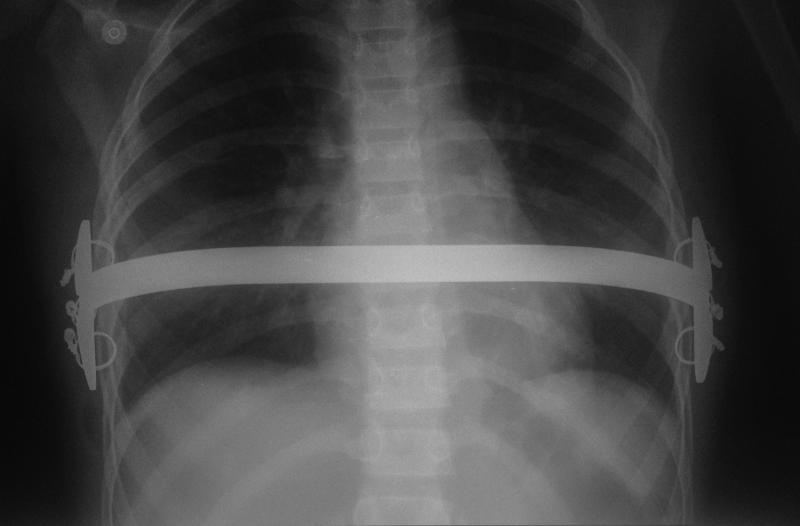

Barra colocada a la Abramson, para corrección de PECTUS CARINATUM LATERAL.